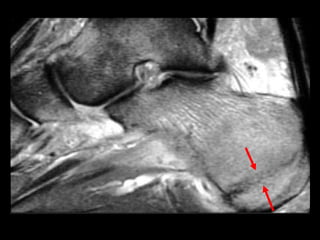

http://www.parksidemri.com/physician/casestudy/case-win03/images/case7.jpg

http://www.parksidemri.com/physician/casestudy/case-win03/fig6.html